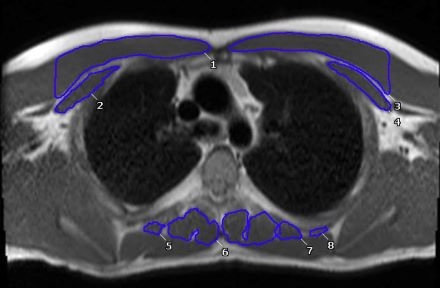

Methods: A retrospective, single-center study was performed, analyzing 75 post-Fontan patients who had CMR completed between 2010 and 2022. The anterior and paraspinal muscles were measured (Figure). COI z-scores were split into low and high levels, and univariate analyses were subsequently performed to determine associations between COI levels, exercise capacity and muscle mass.